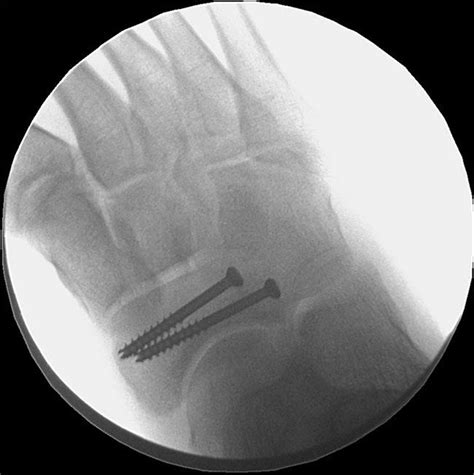

• Order imaging tests such as X-rays, MRI, or bone scans to confirm the diagnosis.

Imaging tests are crucial because stress fractures may not be visible on initial X-rays. An MRI or bone scan can provide a more detailed view of the bone and surrounding tissues.

In some cases, surgery may be required to stabilize the fracture and promote healing. This is typically reserved for severe or non-healing fractures.